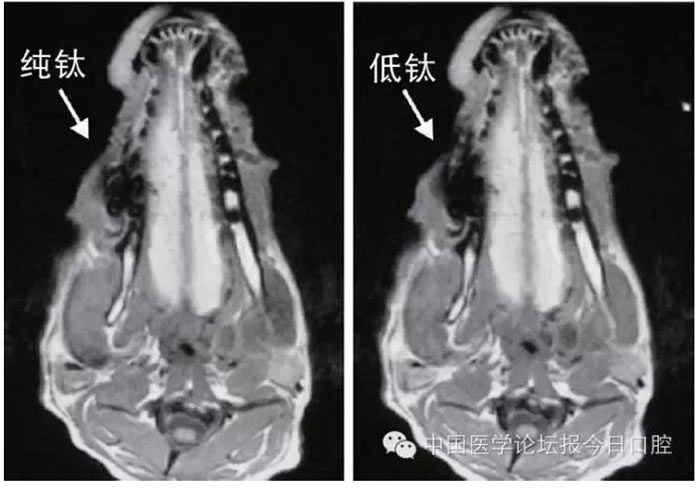

文獻(xiàn)研究中常使用的金屬包括鎳鉻合金、鈷鉻合金、低鈦合金、純鈦、金合金、金鈀合金、銀鈀合金等成分如表所示。大量研究得出近乎一致性的結(jié)論。金合金、金鈀合金、銀鈀合金對MRI影響甚微,與全瓷材料、丙烯酸樹脂極為相似,表現(xiàn)為修復(fù)體影像邊緣光滑、無變形、無偽影;純鈦金屬對MRI影響較小,接近于全瓷材料;但有的研究卻發(fā)現(xiàn)純鈦在核磁共振場中也產(chǎn)生偽影,但偽影涉及的掃描層數(shù)較少;低鈦合金(鈦合金)對MRI影響較大,介于純鈦和鎳鉻合金之間,中度偽影;鎳鉻合金、鈷鉻合金對MRI影響很大,鈷鉻合金更甚;表現(xiàn)為重度偽影、圖像扭曲變形(圖1、圖2)。不難看出,對MRI 影響,全瓷材料、樹脂材料<金合金等貴金屬<純鈦<低鈦合金<鎳鉻合金<鈷鉻合金。有研究發(fā)現(xiàn)鈷鉻合金橋偽影大小與修復(fù)體長軸一致,影響范圍為固定橋近遠(yuǎn)中徑2倍,頰舌徑的4倍;相同外形金屬修復(fù)體厚度增加,偽影增加。單個(gè)金屬樁核偽影可波及到上頜竇、牙槽骨、舌體、舌下腺等組織器官,但對眼底、眼內(nèi)容物、腦組織和頸椎成像基本無影響。

圖2 4種金屬冠在犬MRI檢查中的影響,圖片引自《實(shí)用口腔醫(yī)學(xué)雜志》2014第30期《4種金屬冠對磁共振成像影響的對比研究》一文,作者高嵐等